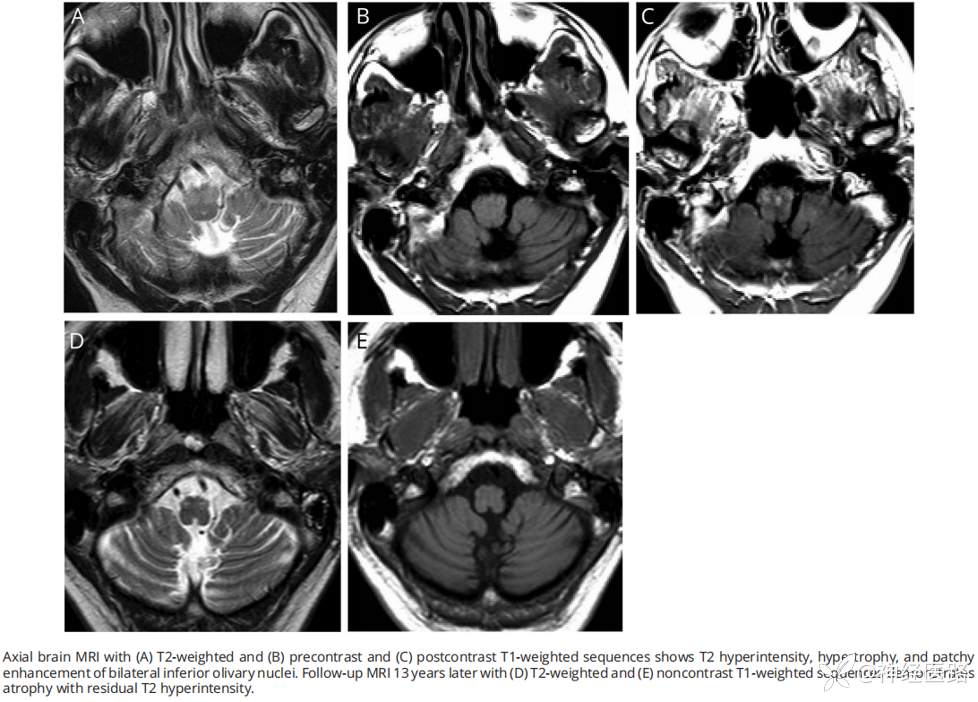

10.进行性共济失调和腭震颤(progressive ataxia and palatal tremor,PAPT):最突出的症状包括视觉异常、构音障碍、吞咽困难、四肢和步态共济失调以及其他与小脑综合征相关的特征。

下图示

A、T2WI;B、T1WI;C、T1增强:MRI可见双侧下橄榄核T2高信号伴肥大和斑片状强化。

D、T2WI;E、T1WI:13年后复查MRI可见双侧下橄榄核萎缩并残留T2高信号。